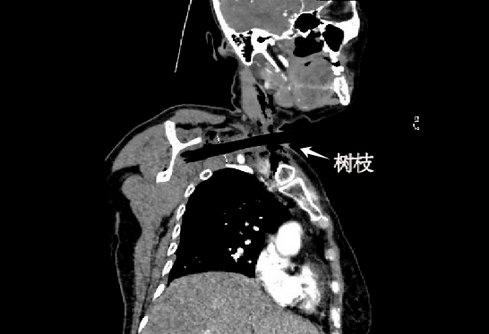

10月25日早晨,田某到达协和急诊科。此时,距离受伤已经过去了14个小时,她疼得说不出话来,血压已经飙升到231/99mmHg。经过医生检查发现,树枝插入的位置格外凶险,离右侧锁骨下动脉、右侧颈总静脉不到5毫米,暴露在体外的断端一直随着血管的搏动而轻轻摇晃。田某的右侧肩胛骨和肋骨还存在多发骨折,加剧了疼痛。

▲患者影像学资料

树枝紧贴血管如同“地雷”。颈部血管神经丰富,解剖结构复杂,时间越长,越容易导致功能受损和严重的深部感染。医务处立即组织骨科、耳鼻喉科、胸外科、血管外科、整形美容外科、基本外科急诊团队、麻醉科、重症医学科、感染内科等多学科会诊。专家们一致认为:必须马上手术。但树枝与颈根部大动脉、神经、锁骨、右肺等人体重要的结构距离极近,稍有不慎就可能出现重大损伤、大出血、瘫痪,甚至致命。